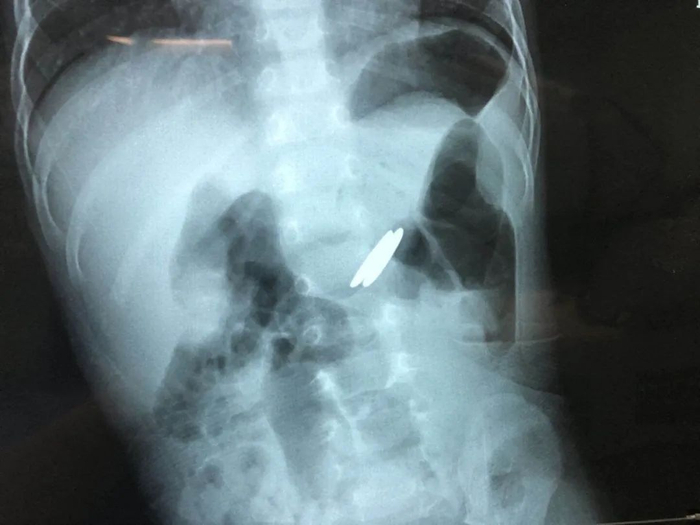

当晚接诊的是宁夏医科大学总医院儿童急诊,做了胸片检查,提示异物位于食道上段,于是请耳鼻喉头颈外科会诊,在局麻下做了食道镜检查,但电池的个头比加大,直径2厘米左右,接近5分钱硬币,而且孩子吞下去的是2枚电池,取出非常困难,甚至滑落到了更深的地方。

医院再次复查正位腹平片,发现电池掉进了胃内,遂转诊到小儿外科。考虑到胃酸腐蚀电池后会引起电池内部化学物质泄露,引起中毒及消化道损伤,小儿外科立即收住院,同时联系消化内科及麻醉科,准备做手术,通过胃镜探查并取出电池。